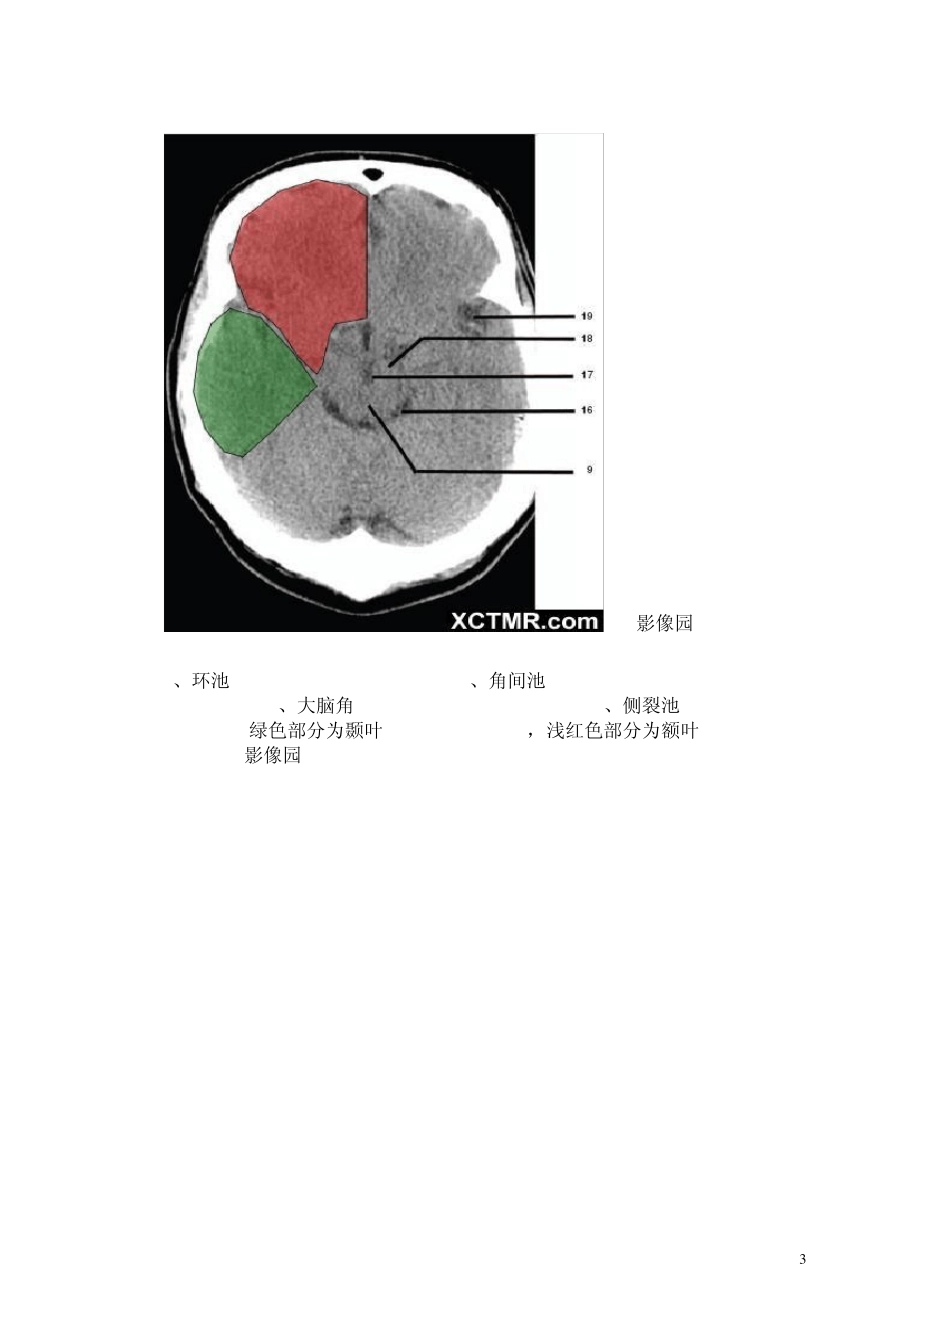

1 颅脑CT解剖(图文) skC影像园XCTMR.com 1、蝶窦(Sphenoid sinus) 2、延髓 (Medulla oblongata) 3、小脑 (cerebellum) 绿色部分为颞叶(Temporal Lobe),浅红色部分为额叶(Frontal Lobe)skC影像园XCTMR.com skC影像园XCTMR.com skC影像园XCTMR.com 2 4、第四脑室(Fourth ventricle) 5、小脑中角(Middle cerebellar peduncle) 6、乙状窦(Sigmoid sinus) 7、颞骨及乳突气房 (Petrous temporal bone and mastoid air cells) 8、桥小脑角(Cerebellopontine angle) 9、脑桥 (Pons) 10、垂体窝(Pituitary fossa) 绿色部分为颞叶(Temporal Lobe),浅红色部分为额叶(Frontal Lobe)skC影像园 XCTMR.com skC影像园 XCTMR.com 11、小脑蚓部(Cerebellar vermis) 12、基底动脉(Basilar artery) 13、桥前池 (Prepontine cistern) 14、鞍背 (Dorsum sellae) 15、侧脑室颞角(Temporal horn of lateral ventricle) 绿色部分为颞叶(Temporal Lobe),浅红色部分为额叶(Frontal Lobe)skC影像园 XCTMR.com 3 skC影像园XCTMR.com 16、环池 (Ambient cistern) 17、角间池 (Interpeduncular cistern) 18、大脑角 (Cerebral peduncle) 19、侧裂池 (Sylvian fissure) 绿色部分为颞叶(Temporal Lobe),浅红色部分为额叶(Frontal Lobe) skC影像园XCTMR.com 4 skC影像园XCTMR.com 20、小脑上池 (Third ventricle) 21、侧脑室前角 (Frontal horn of lateral ventricle) 21a、第三脑室 (Third ventricle) 绿色部分为颞叶(Temporal Lobe),浅红色部分为额叶(Frontal Lobe),黄色部分为枕叶(Occipital Lobe)skC影像园XCTMR.com 5 skC影像园XCTMR.com 22、尾状核头部 (Head of caudate nucleus) 23、岛叶 (Insular cortex) 24、外囊 (External capsule) 25、豆状核(Lentiform nucleus) 26、丘脑(Thalamus) 绿色部分为颞叶(Temporal Lobe),浅红色部分为额叶(Frontal Lobe),黄色部分为枕叶(Occipital Lobe)skC影像园XCTMR.com 6 skC影像园XCTMR.com 27、纵裂 (Interhemispheric fissure) 28、内囊前肢 (Anterior limb of internal capsule) 29、内囊膝部 (Genu of internal capsule) 30、内囊后肢(Posterior limb of internal capsule) 31、侧脑室三角区及脉络丛钙化(Trigone of lateral ventricle and calcified choroid plexus)...